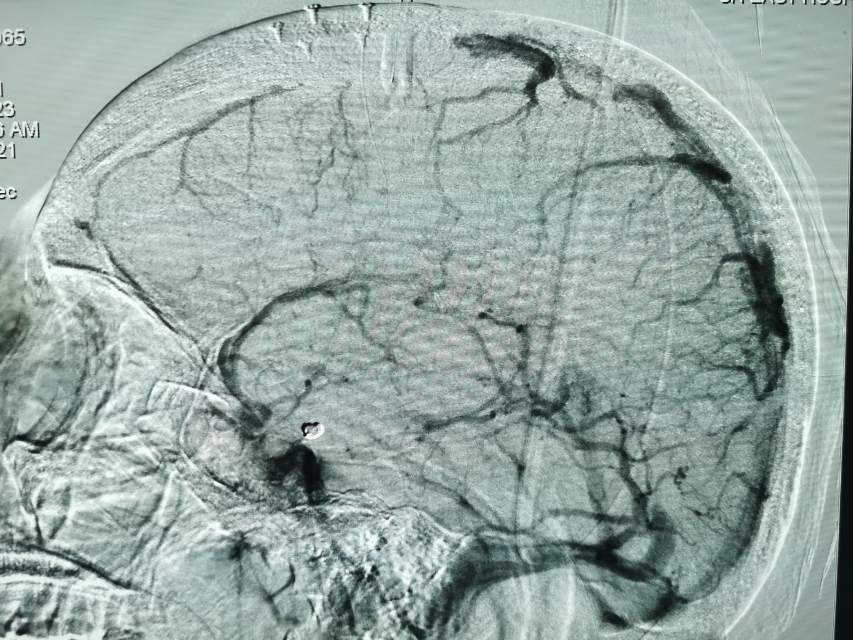

然而,动脉瘤栓塞完毕,我们发现由于肝素的使用,直窦及其分支系统显影明显好转,提示局部血栓的存在;同时,上矢状窦前1/3也明显显影不良,提示血栓的存在,整个静脉窦的显影时间明显滞后3-4秒。所有这些,都支持CVST的存在。

3、处理措施:急诊法舒地尔灌注+肝素灌注。执行时间:出现后6小时执行。术中发现:上矢状窦系统后2/3也显影隐约中断,错错落落,直窦及其属支显影也不太好